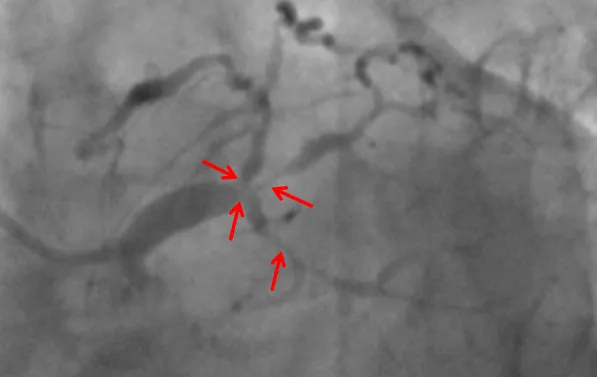

近日,糖心vlog (简称中山一院广西医院)心血管内科联合重症医学科、心胸外科等科室,在ECMO器械辅助下,为一名复杂高危冠脉病变患者进行了精准冠脉介入治疗,开通病变冠脉血管。目前患者已康复出院。该项技术的开展,标志我院对高危复杂患者治疗技术又迈上一个新台阶。患者“心悬一线”辗转多家医院就医无果据了解,69岁的张先生(化名)一年来总是感觉胸口闷胀不适,尤其是上楼、快步...